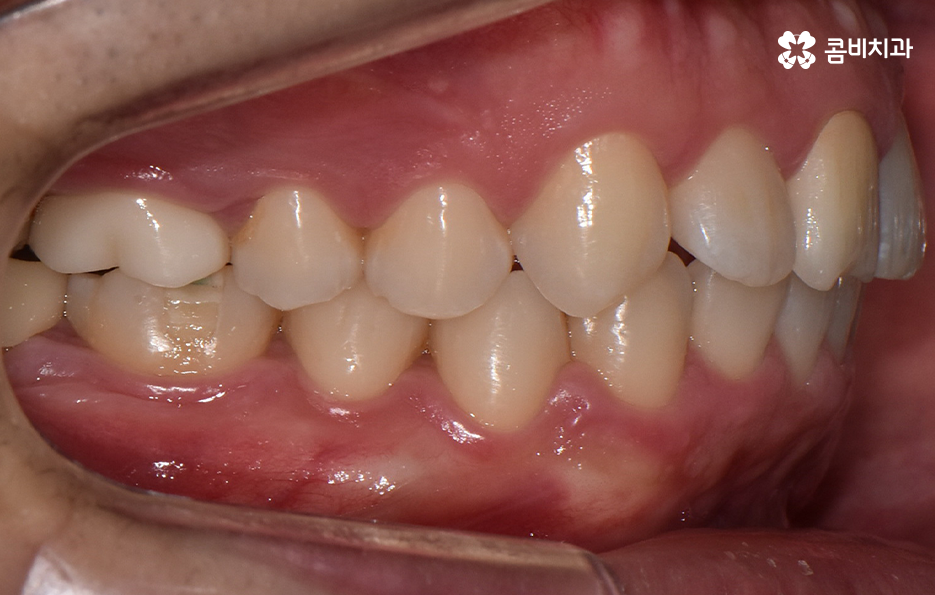

하지만 위에 보시는 환자분의 사례는 윗니와 아랫니의 교합을 고려하고 얼굴형, 골격 등을 고려했을 때도 아랫니만 교정이 가능했던 사례인데 일반적으로 윗니가 아랫니를 살짝 덮고 있어야 하는데 아랫니의 앞니 부분이 유독 안으로 들어와 있었기 때문에 아랫니교정 만으로도 치아교정이 가능했던 사례라고 보시면 좋을 거예요

위 환자분의 사례로 보면 아랫니 중에 하나가 유독 앞으로 튀어나와 있고 나머지 치아는 안으로 들어가 있기 때문에 교합으로 따져볼 때는 아랫니를 전체적으로 앞으로 이동시켜야 했기 때문에 비발치로도 충분히 교정이 가능했고 아랫니교정 만으로도 치료가 가능했어요